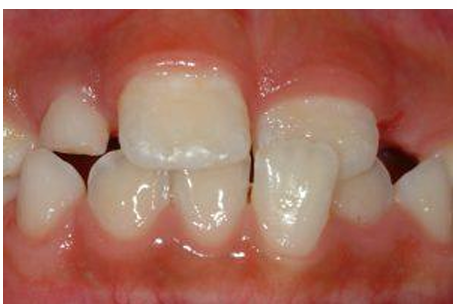

MFD EXAMS /23 6 1234567891011121314151617181920212223 You have 30 min to complete this exam. The timer will start once you begin Attention: Only a few minutes left! Please submit your answers soon. MFD 1 Get a quick sneak peek before the real exam !This trial quiz is designed to show you the question style, difficulty level, and how the options will appear on the platform. 1 / 23 1. What is the lethal dose and toxic dose of fluoride, management? Check 2 / 23 2. What the advantage of silver diamine over other methods and disadvantages ? Check 3 / 23 3. Method of topical fluoride application with concentration ? Check 4 / 23 4. What will happen if left untreated? Check 5 / 23 5. What changes that will happen if the habit stopped? Check 6 / 23 6. Give 3 of your initial stage of treatment? Check 7 / 23 7. What are the causes? Check 8 / 23 8. What is this? Check 9 / 23 9. Then they specified the type of pain and asked about the diagnosis Check 10 / 23 10. What other tests to check vitality of the pulp? Check 11 / 23 11. What are the factors will govern the Rx of Posterior cross bite ? Check 12 / 23 12. What are the factors that govern the treatment of anterior cross bite? Check 13 / 23 13. Name the appliance that you can use to treat this case? Check 14 / 23 14. Name 3 causes? Check 15 / 23 15. Name the most important clinical diagnostic information you need to know. (check RCSI intensive course )? Check 16 / 23 16. What do you see? Check 17 / 23 17. What is your treatment? Check 18 / 23 18. Name the investigations needed? Check 19 / 23 19. causes for gingival enlargement ? Check 20 / 23 20. What is the common side effect of this drug? Check 21 / 23 21. Name the drug that he may take to treat this condition? Check 22 / 23 22. The patient may have what? Check 23 / 23 23. What is this clinical condition? Check /31 2 12345678910111213141516171819202122232425262728293031 You have 30 min to complete this exam. The timer will start once you begin Attention: Only a few minutes left! Please submit your answers soon. MFD 2 Get a quick sneak peek before the real exam !This trial quiz is designed to show you the question style, difficulty level, and how the options will appear on the platform. 1 / 31 1. Mention 2 fixed space maintainers and 2 removable space maintainers other from mentioned : Check 2 / 31 2. Other space maintenance used for child lost primary second molar E before the eruption of the permanent molars ? Check 3 / 31 3. What are the difference between nance appliance and Transpalatal arch Check 4 / 31 4. What material used to attach band? Check 5 / 31 5. What instruction you give to patient? Check 6 / 31 6. Name other fixed space maintainer used in upper jaw and mechanism of their action? Check 7 / 31 7. What component of this appliance? Check 8 / 31 8. What is this appliance , for what its used ? Check 9 / 31 9. Treatment? Check 10 / 31 10. Define Abrasion and Erosion? Check 11 / 31 11. What does this picture show? Check 12 / 31 12. what investigations you can do ? Check 13 / 31 13. Drugs can lead to lichenoid reaction Check 14 / 31 14. What extra oral features in “ Lichenoid reaction )? Check 15 / 31 15. What microscopical features of it ( licheonoid reaction )? Check 16 / 31 16. Definitive diagnosis ? Check 17 / 31 17. Mention type of suggested biopsy ? Check 18 / 31 18. Mention 4 differential diagnosis ? Check 19 / 31 19. Mention 4 questions you will ask the patient ? Check 20 / 31 20. Give 4 intraoral decription of what you see ? Check 21 / 31 21. What the other surgery can be performed to make prothesis? Check 22 / 31 22. Can this tooth stand with fixed prothesis? (in the opg )à taken from Malek file ? Check 23 / 31 23. Radiograph of missing multiple teeth consider it according to Antes law? ON which tooth you will make Abutment ? Check 24 / 31 24. What is Antes law? Check 25 / 31 25. What is best one to use as abutment in fixed prosthesis A or B? Check 26 / 31 26. What relevance of this picture? Check 27 / 31 27. What’s complication of doing surgery in this area floor of mouth? Check 28 / 31 28. Other 2 radiograph needed in diagnosis? Check 29 / 31 29. Give 4 differential diagnosis? Check 30 / 31 30. What can you see ? Check 31 / 31 31. What is the name of radiograph? Check Your score is /30 1 123456789101112131415161718192021222324252627282930 You have 30 min to complete this exam. The timer will start once you begin Attention: Only a few minutes left! Please submit your answers soon. MFD 3 Get a quick sneak peek before the real exam !This trial quiz is designed to show you the question style, difficulty level, and how the options will appear on the platform. 1 / 30 1. Treatment? Check 2 / 30 2. Histopathology? Check 3 / 30 3. Differential diagnosis Check 4 / 30 4. Clinical features’? Check 5 / 30 5. Patient said, this lesion is very frequent, why? Check 6 / 30 6. What are the causes for ulcers? Check 7 / 30 7. Patient have other signs like uveitis ,Genital ulcerations which syndrome he had ? Check 8 / 30 8. Name of the lesion ? Check 9 / 30 9. Mention some TMJ movement ? Check 10 / 30 10. Blood supply ? Check 11 / 30 11. Nerve supply ? Check 12 / 30 12. Which muscles close? Check 13 / 30 13. Action of open and open wide? Check 14 / 30 14. Why it’s Atypical joint ? Check 15 / 30 15. Name of the ligaments ? Check 16 / 30 16. What would be your management? Check 17 / 30 17. Bacteria involved Check 18 / 30 18. Which type of Periodontitis? Check 19 / 30 19. Treatment? Check 20 / 30 20. Histopathology? Check 21 / 30 21. Differential diagnosis? Check 22 / 30 22. Clinical features? Check 23 / 30 23. What are the time frames for making a complaint? Check 24 / 30 24. What are the 3 points related to negligence? Check 25 / 30 25. Who is allowed access to the patient records? Check 26 / 30 26. How to differentiate if it is upper or lower motor neuron lesion? Check 27 / 30 27. Management? Check 28 / 30 28. What are the causes? Check 29 / 30 29. What should you advise the patient to do? Check 30 / 30 30. What is this lesion? Check Your score is /24 1 123456789101112131415161718192021222324 You have 30 min to complete this exam. The timer will start once you begin Attention: Only a few minutes left! Please submit your answers soon. MFD 4 Get a quick sneak peek before the real exam !This trial quiz is designed to show you the question style, difficulty level, and how the options will appear on the platform. 1 / 24 1. What does MRONJ stands for? Check 2 / 24 2. Give definition for MRONJ Check 3 / 24 3. For what medical problems these medications are used? Check 4 / 24 4. Stages of MRONJ 3 Check 5 / 24 5. What’s this appliance? Check 6 / 24 6. At what age is it used? Check 7 / 24 7. What type of malocclusion is it used to treat? Check 8 / 24 8. What changes will produce? (4 options) Check 9 / 24 9. Disadvantages? Check 10 / 24 10. Why is it flabby tissue? Check 11 / 24 11. what is this condition called? Check 12 / 24 12. Causes ? Check 13 / 24 13. Clinical Features ? Check 14 / 24 14. How to avoid it ? Check 15 / 24 15. Management? Check 16 / 24 16. Ideal post length and width Check 17 / 24 17. Definition of Ferrule it’s the Check 18 / 24 18. What is the importance of the ferrule effect ? Check 19 / 24 19. Describe the radiolucency? Check 20 / 24 20. Give 6 differential diagnosis? Check 21 / 24 21. Give 5 radiographical features? Check 22 / 24 22. What is the difference between incisional and excisional biopsy? Check 23 / 24 23. What other 2 plain radiographs we can we can take? Check 24 / 24 24. ALARA? Check Your score is /22 1 12345678910111213141516171819202122 You have 30 min to complete this exam. The timer will start once you begin Attention: Only a few minutes left! Please submit your answers soon. MFD 5 Get a quick sneak peek before the real exam !This trial quiz is designed to show you the question style, difficulty level, and how the options will appear on the platform. 1 / 22 1. . Types of external root resorption? Check 2 / 22 2. The cause of root resorption in the pic? Check 3 / 22 3. How you will treat it? Check 4 / 22 4. What is this probe? Check 5 / 22 5. What is the mark a ? Check 6 / 22 6. What is the mark b ? Check 7 / 22 7. What is the score from the given reading? Check 8 / 22 8. What is the treatment need of the patient according to the score? Check 9 / 22 9. What is the differential diagnosis ? Check 10 / 22 10. Four clinical features of the lesion? Check 11 / 22 11. Treatment ? Check 12 / 22 12. Describe what do you see? Check 13 / 22 13. Causes for it ? Check 14 / 22 14. Treatment ? Check 15 / 22 15. Picture of patient with Anaphylaxis…after taking Check 16 / 22 16. What is diagnosis? - Check 17 / 22 17. What a the signs of Anaphyalxis reactions ? Check 18 / 22 18. What first line of treatment? Dose? Route of Adminstration? Check 19 / 22 19. Other drug used? Check 20 / 22 20. What are expected complications if not treated ? Check 21 / 22 21. What precautions should be made to prevent anaphylaxis reaction ? - Check 22 / 22 22. Name 10 drug in emergency used with their route of Administration and their condition they use in? Check Your score is /36 1 123456789101112131415161718192021222324252627282930313233343536 You have 30 min to complete this exam. The timer will start once you begin Attention: Only a few minutes left! Please submit your answers soon. MFD 6 Get a quick sneak peek before the real exam !This trial quiz is designed to show you the question style, difficulty level, and how the options will appear on the platform. 1 / 36 1. . What are cases that you have to extract the primary tooth? Check 2 / 36 2. D. What are the indications for extraction? Check 3 / 36 3. What are your treatment options? Check 4 / 36 4. Investigations? Check 5 / 36 5. Type of trauma? Check 6 / 36 6. Patient diagnosed with sjorgen syndrome Histology ? - Check 7 / 36 7. Patient diagnosed with sjorgen syndrome Mention four blood investigations ? Check 8 / 36 8. Patient diagnosed with sjorgen syndrome Mention two sites where can we take the biopsy Check 9 / 36 9. Patient diagnosed with sjorgen syndrome How can you differentiate between primary and secondary ? Check 10 / 36 10. Gingival inflammation present in which syndrome Check 11 / 36 11. What is the treatment? Check 12 / 36 12. mention another connective tissue disease that can lead to lesions “ intraorally “ similar to the Lichen planus ? Check 13 / 36 13. what serious complication can arise from Erosive lichen planus ? Check 14 / 36 14. If it was atrophic lesion what histology might be seen ? Check 15 / 36 15. List the histological features of lichen planus ? Check 16 / 36 16. Lichen planus what dose it affect? Check 17 / 36 17. Age group commonly affected ? -ref SAQ Check 18 / 36 18. What are the clinical presentation ‘ types of lichen planus ‘ Check 19 / 36 19. What might you see in patient’s body that has a relation to this lesion? Check 20 / 36 20. What are the differential diagnoses? Check 21 / 36 21. Factors for platelet adhesion? Check 22 / 36 22. What can you see? Check 23 / 36 23. Other 2 process of hemostasis? Check 24 / 36 24. Two diseases in which they increase ? Check 25 / 36 25. Two diseases in which they decrease? Check 26 / 36 26. Medical term when they decrease? And if they increased Check 27 / 36 27. Function Check 28 / 36 28. Life span ? Check 29 / 36 29. From where they arise? Check 30 / 36 30. Normal number? Check 31 / 36 31. What are the function of the guiding plane ? Check 32 / 36 32. The success rate ? Check 33 / 36 33. Mention single extra preparation requirement for Resin bonded bridge in posterior teeth ? Check 34 / 36 34. Mention 5 preparation features of it? Check 35 / 36 35. Give two advantages of it ? Check 36 / 36 36. What’s the name of this prosthesis? Check Your score is /23 1 1234567891011121314151617181920212223 You have 30 min to complete this exam. The timer will start once you begin Attention: Only a few minutes left! Please submit your answers soon. MFD 7 Get a quick sneak peek before the real exam !This trial quiz is designed to show you the question style, difficulty level, and how the options will appear on the platform. 1 / 23 1. If the same scenario but the tooth is subluxated. What is the management? Check 2 / 23 2. Aim of this procedure Check 3 / 23 3. Steps to do this procedure? Check 4 / 23 4. Management? How to asses the vitality of the tooth Check 5 / 23 5. Mention factors that can affect the treatment plan ? Check 6 / 23 6. Identify the Kenneyd’s classification Check 7 / 23 7. Name its parts? Check 8 / 23 8. Uses of Surveyor Check 9 / 23 9. What is this ? Check 10 / 23 10. Criteria for hand piece sterilization Check 11 / 23 11. steps for wrapped instrument sterilization process ( ref : sterilization in SDCEP)? Check 12 / 23 12. What is the difference between sterilization and decontamination? Check 13 / 23 13. Optimal temperature & pressure & time for autoclave? Check 14 / 23 14. Difference between vacuum and non-vacuum autoclave in mechanism? Check 15 / 23 15. Optimum temperature? Check 16 / 23 16. Advantage of vaccum over non vaccum? Check 17 / 23 17. What is the significance of forehead wrinkling? Check 18 / 23 18. What is Ramsy haunt syndrome ? Rx ? and is it LMN or UMN ? Check 19 / 23 19. Enumerate 3 extracranial and intracranial causes for this ? Check 20 / 23 20. What are the branches of facial nerve? Check 21 / 23 21. Why do we suture the eye in a patient with Facial Palsy? Check 22 / 23 22. Differentiate between Upper and Lower Motor Neuron lesions? Check 23 / 23 23. What is shown in photograph? Check Your score is /27 0 123456789101112131415161718192021222324252627 You have 30 min to complete this exam. The timer will start once you begin Attention: Only a few minutes left! Please submit your answers soon. MFD 8 Get a quick sneak peek before the real exam !This trial quiz is designed to show you the question style, difficulty level, and how the options will appear on the platform. 1 / 27 1. Mention 4 diseases you would see in HIV Patients? Check 2 / 27 2. Give 2 differential diagnosis for this lesion? Check 3 / 27 3. Describe the lesion shown in Photograph B? Check 4 / 27 4. What is your diagnosis ? Check 5 / 27 5. Describe the lesion shown in Photograph A? Check 6 / 27 6. Disadvantages of gold ? Check 7 / 27 7. Ideal cement for All Porcelain? Check 8 / 27 8. Which cement would u use for high caries risk patient? Check 9 / 27 9. How much would you prepare for functional and non-functional cusps in Gold Crown? Check 10 / 27 10. what crown would you go for in bruxism patients out of these 3? Check 11 / 27 11. Name the 3 restorations? Check 12 / 27 12. After administering Local Anesthesia and deciding the choice of biopsy. What should be done before biopsying the lesion? Check 13 / 27 13. Name 2 systemic steroids with dosage you would recommend for this patient? Check 14 / 27 14. Name 2 topical steroids with dosage you would recommend for this patient? Check 15 / 27 15. What is your diagnosis? Check 16 / 27 16. Describe the lesion shown in photograph? Check 17 / 27 17. Name 5 options to increase retention and stability in class l Check 18 / 27 18. E. What is the function of the RPI system ? Check 19 / 27 19. What are the 2 disadvantages of the 2 restorations you mentioned? Check 20 / 27 20. What materials are your 2 restorations made of? Check 21 / 27 21. Other than implants what restoration would you place in this patient? Check 22 / 27 22. Which Kennedy’s classification is this? Check 23 / 27 23. Describe your management? Check 24 / 27 24. What may be the patient complaint? Check 25 / 27 25. What are the causes of this? Check 26 / 27 26. Describe what you see in the photograph? Check 27 / 27 27. which 4 examinations would you undertake? Check Your score is /31 0 12345678910111213141516171819202122232425262728293031 You have 30 min to complete this exam. The timer will start once you begin Attention: Only a few minutes left! Please submit your answers soon. MFD 9 Get a quick sneak peek before the real exam !This trial quiz is designed to show you the question style, difficulty level, and how the options will appear on the platform. 1 / 31 1. Describe what you see in the photograph? Check 2 / 31 2. Three other features of this syndrome ? Check 3 / 31 3. What is the medical condition associated with it “? Multiple OKC? Check 4 / 31 4. Where expansion occurs in the OKC ? Check 5 / 31 5. From which cells this lesion arises from? Check 6 / 31 6. What is your diagnosis? Check 7 / 31 7. What is the histopathology of the lesion shown in Histology slide? Check 8 / 31 8. Give 4 differential diagnosis? Check 9 / 31 9. What is the consequence of premature loss of deciduous teeth? Check 10 / 31 10. Identify those appliances and mention one use for each and mode of action? Check 11 / 31 11. What component of appliance no. 3 ? Check 12 / 31 12. How to overcome open bite disadvantage ? Check 13 / 31 13. What are Disadvantages of this appliance ? Check 14 / 31 14. What Ceph changes are expected while using this appliance ? Check 15 / 31 15. What is the construction of Twin Block Appliance? Check 16 / 31 16. What skeletal and dental changes are expected while using this appliance ? Check 17 / 31 17. What is the ideal age to treat this condition >? Check 18 / 31 18. Indications of the Twin Block Appliance? Two Check 19 / 31 19. Name the Appliance used to correct this? Check 20 / 31 20. What is the treatment? Check 21 / 31 21. How to prevent it Check 22 / 31 22. Mention three mechanisms of action of Fluoride? Check 23 / 31 23. What is the disease caused by excess Fluoride? Check 24 / 31 24. What are the risk factors associated with this patient? Check 25 / 31 25. Name the principal organism causing this? Check 26 / 31 26. what are the principles of the access cavity Check 27 / 31 27. What is your diagnosis? Check 28 / 31 28. What are principles of cavity preparation? Check 29 / 31 29. What is your Periapical diagnosis? Check 30 / 31 30. What is your Pulpal diagnosis? Check 31 / 31 31. Which test would you undertake? Check Your score is /21 0 123456789101112131415161718192021 You have 30 min to complete this exam. The timer will start once you begin Attention: Only a few minutes left! Please submit your answers soon. MFD 10 Get a quick sneak peek before the real exam !This trial quiz is designed to show you the question style, difficulty level, and how the options will appear on the platform. 1 / 21 1. Patient is 20 years old Mention two treatment options for this case ? Check 2 / 21 2. Patient is 20 years old What is the long term risk for not treating this case ? Check 3 / 21 3. Name of this appliance in the next picture? Check 4 / 21 4. What is the wire used ? Check 5 / 21 5. For which orthodontic cases this appliance is necessary ? Check 6 / 21 6. Why we use retainer ? Check 7 / 21 7. Describe what you see ? Check 8 / 21 8. Differential diagnosis:- Check 9 / 21 9. Name of those muscles ? Check 10 / 21 10. Name the Extrinsic muscles of the tongue? Check 11 / 21 11. . Which nerves innervate the Extrinsic muscles of the tongue?. Check 12 / 21 12. What is the somatic innervation of anterior 2/3 of tongue? Check 13 / 21 13. Which nerve supplies the posterior 1/3 of tongue?. Check 14 / 21 14. From which Pharyngeal arch posterior 1/3 derived from? Check 15 / 21 15. Mention the intrinsic muscle of the tongue ? Check 16 / 21 16. What is the name of this condition ? name the lesion on the skin ? Check 17 / 21 17. Mention 3 drugs that causing it ? Check 18 / 21 18. 2 infections associated with it Check 19 / 21 19. Mention 2 immediate treatment ? Check 20 / 21 20. Why this condition can be fatal ? Check 21 / 21 21. Which test would you undertake? Check Your score is